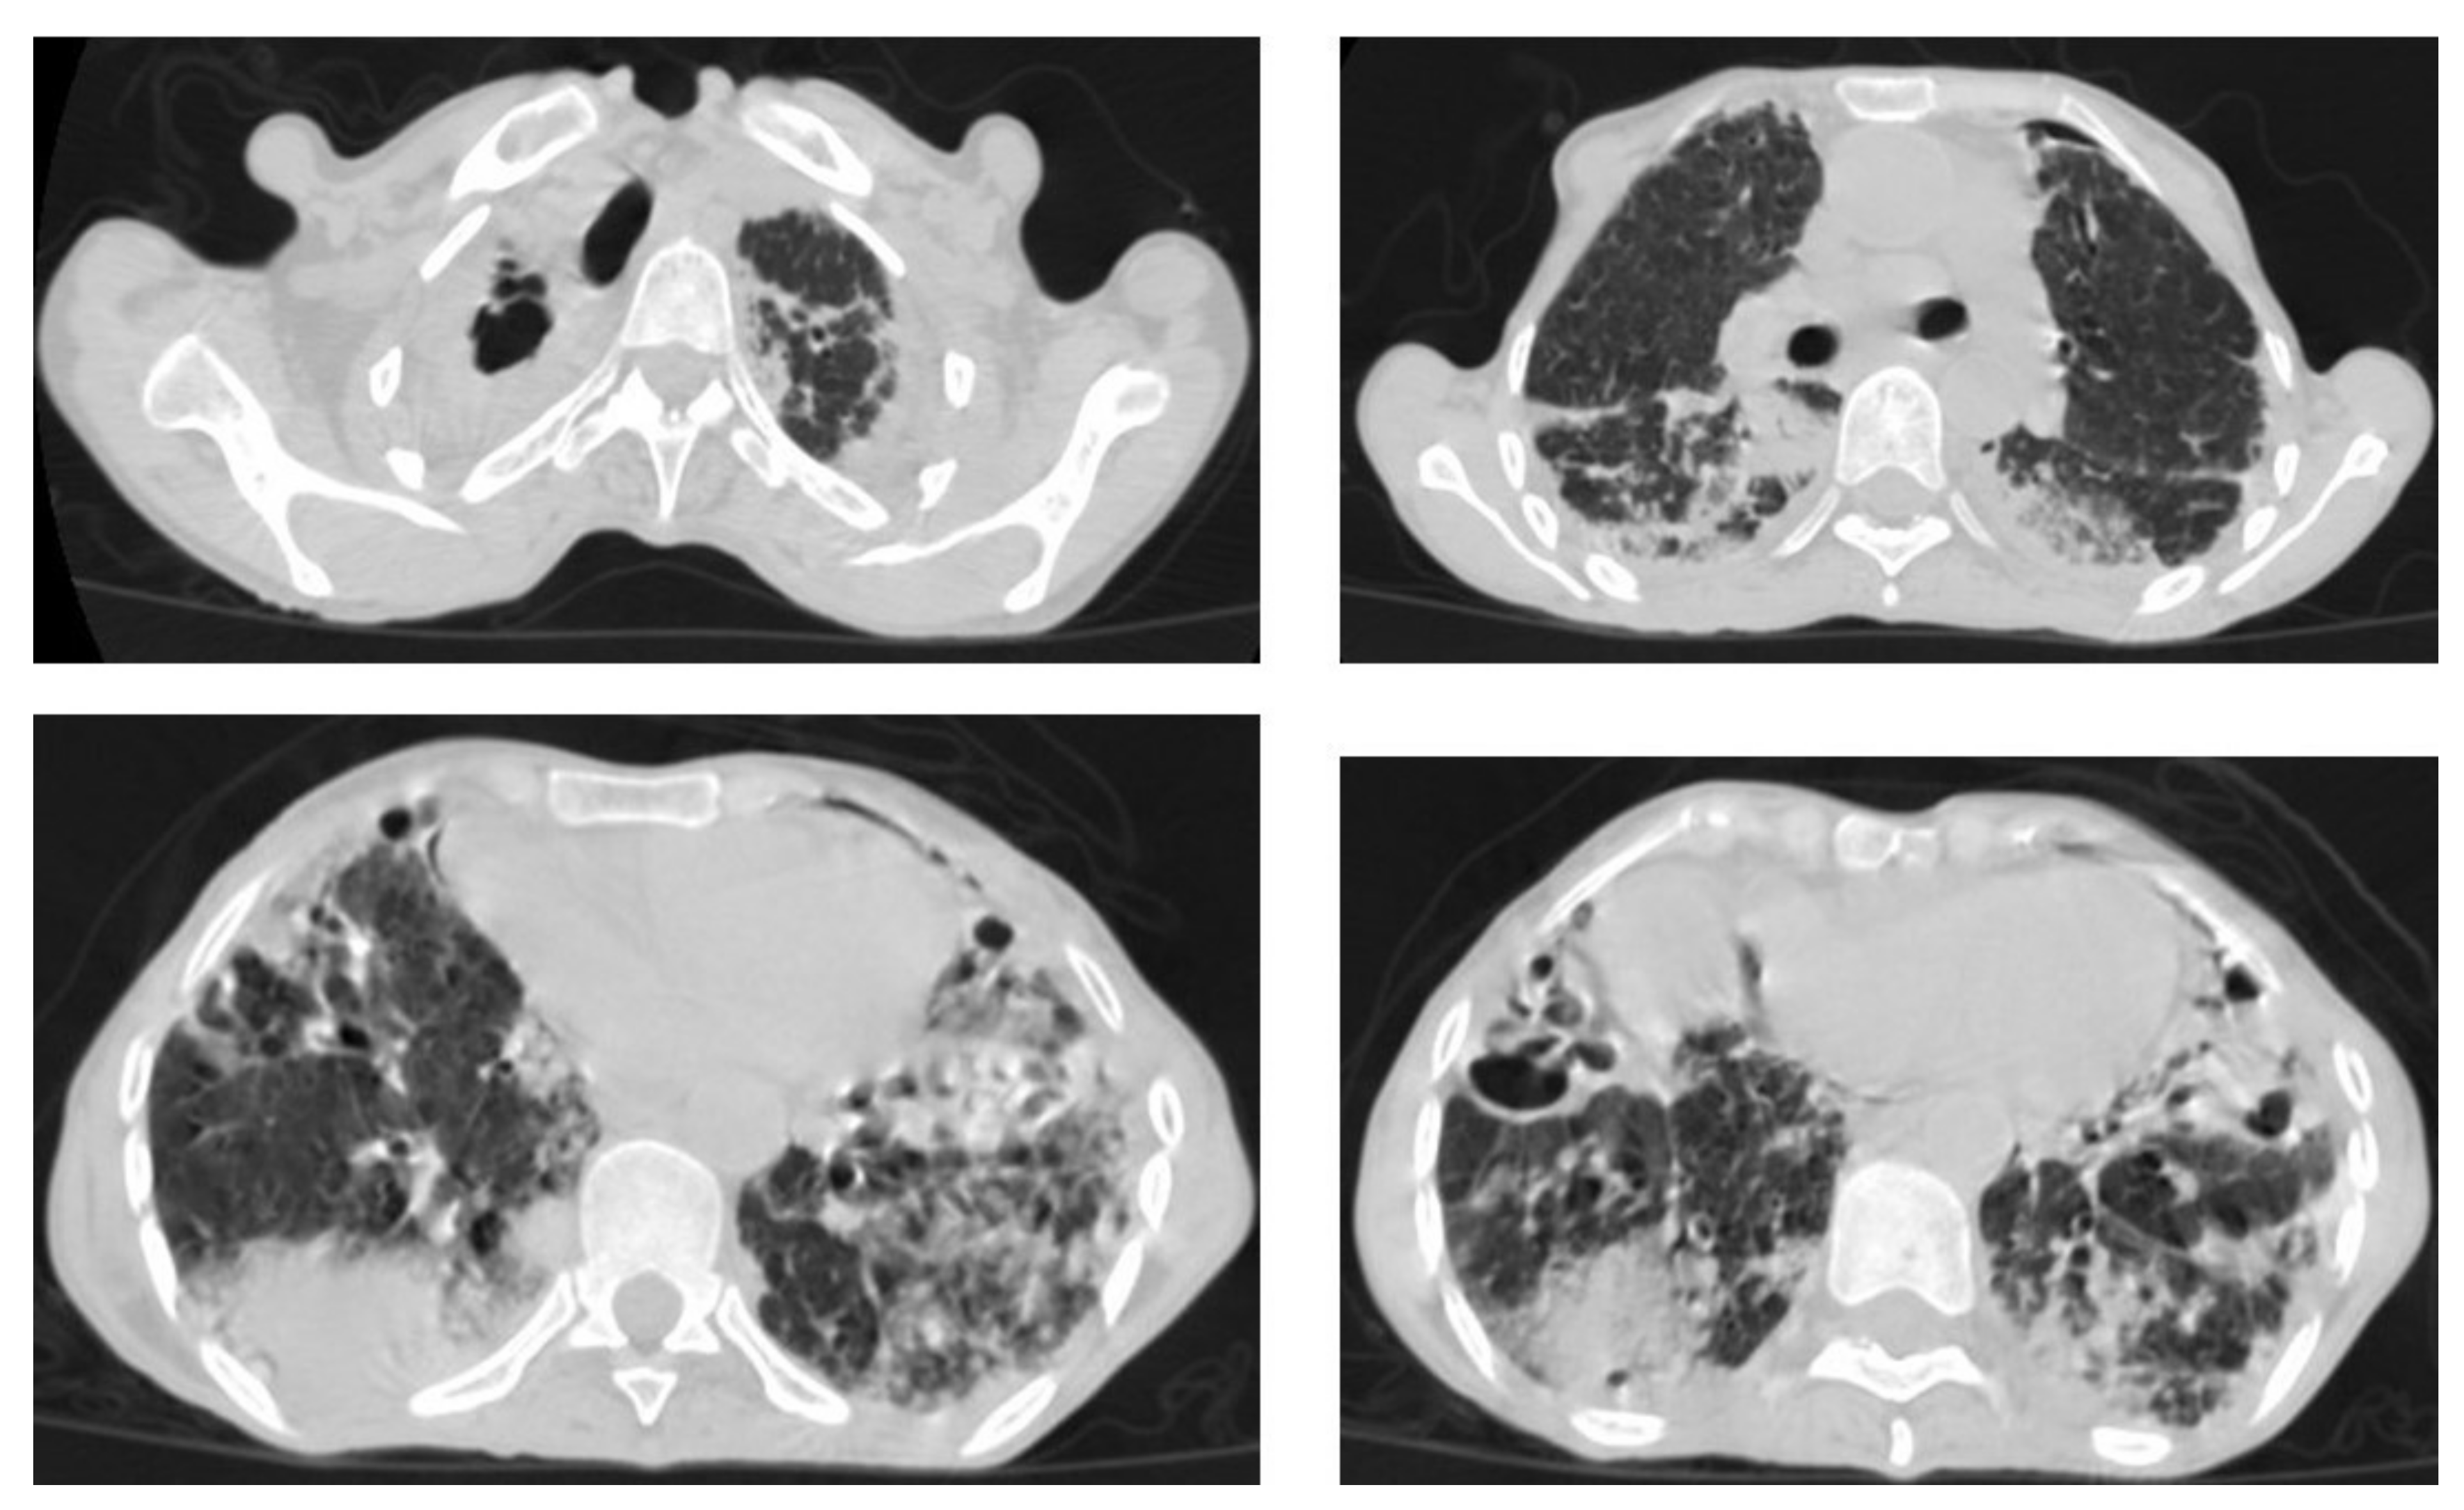

• Miliary TB (Figure 6 and Figure 7) appears as innumerable small (1–3 mm) granulomas with random distribution in the lungs and other organs with a predominance to the lung bases due to the gravity-dependent high blood flow. It occurs due to the hematogenous dissemination of mycobacterium tuberculosis bacilli, especially in immunocompromised patients and children [1,13]. Miliary TB is a significant differential diagnosis of pulmonary metastasis from thyroid cancer or others, even in children [19].

Figure 6. Miliary TB in an 18-year-old man (same patient of Figure 1). (a) Chest radiograph shows superimposed innumerable small nodules in lungs right greater than the left predominantly affecting lung bases due to gravity-dependent high blood flow. (b) Axial chest CT shows innumerable small (1–3 mm) nodules with random distribution in both lung fields.

Figure 9. Old reactive TB with superimposed infection in a 75-year-old female with chronic cough and no history of previous medication. Selected axial images of lung CT show prominent fibrotic changes with scarring traction bronchiectasis and decreased volume in the apical and posterior segment of the upper lobes and architectural distortion of the lung parenchyma caused by cystic bronchiectasis predominantly involve bilateral lower lobes, ligula, and right middle lobe. Patchy consolidative areas and ground glass opacities are signs of active infection.

Figure 10. Reactivation of TB in an adult man with chronic cough. Selected axial images of lung CT show cystic bronchiectasis, due to old infection, with peribronchial thickening and air fluid level involving both lower lobes. Scattered tree in bud pattern and infected cystic bronchiectasis indicate active TB.